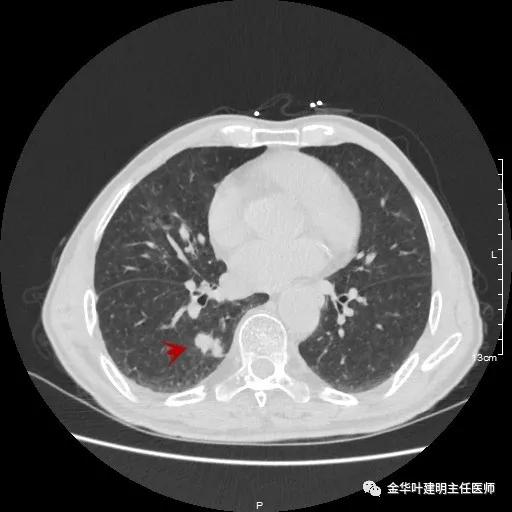

以上示左上叶病灶2。病灶虽然似慢性炎,但有收缩力,有毛刺征,在右侧诸多病灶考虑多原发肺癌的前提下,此灶是恶性的可能性非常大,不能单纯认为其是慢性炎性病灶。就此单灶来看,可以局部切除病检,若示浸润性腺癌,则有肺叶切除的指征。